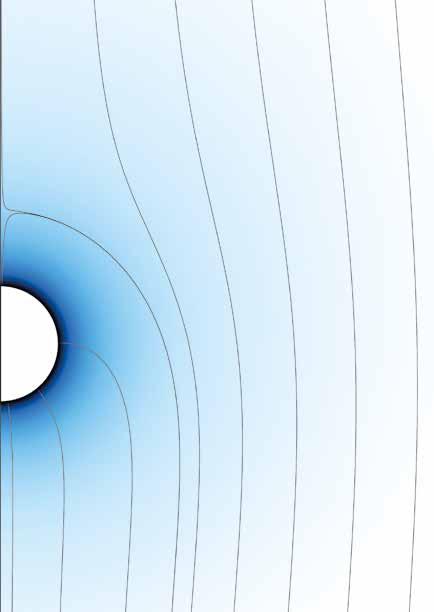

Luminescence thermometry map of newly developed near infrared thermometers. The blue line represents 20°C, the red line 60°C. The ratio of the two peaks is used to build a calibration curve.

thermometry can also be used as a feedback tool,” continues Professor Kaczmarek. “For example, if you want to combine thermometry and photothermal therapy to treat a tumour then you need feedback.”

The cancerous tissue would need to be heated to a high temperature, but it would also be extremely important to avoid over-heating nearby tissue and causing new problems. These nanoparticles could provide rapid feedback to a clinician in these kinds of circumstances,